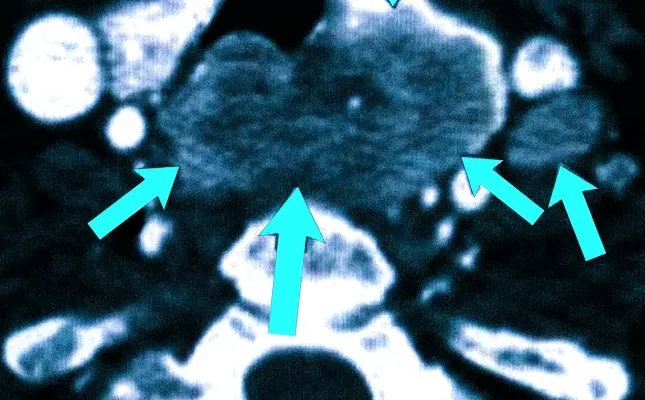

Диагностика рака щитовидной железы: как ультразвук помогает в раннем выявлении Рак щитовидной железы — это одна из наиболее часто встречающихся онкологических